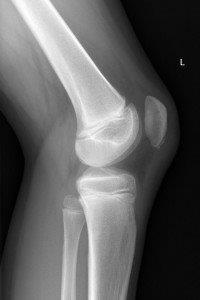

Imaging

- A knee X-ray should have Anterior Posterior (AP) and lateral views and include the distal third of the femur and proximal third of the tibia and fibula.

- Request patella (skyline) views if fractured patella suspected.